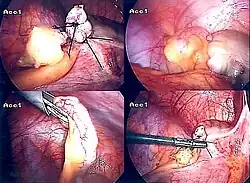

Laparoscopic appendectomy

Laparoscopic appendectomy was introduced in 1983 and has become an increasingly prevalent intervention for acute appendicitis.[95] This surgical procedure consists of making three to four incisions in the abdomen, each 0.25 to 0.5 inches (6.4 to 12.7 mm) long. This type of appendectomy is made by inserting a special surgical tool called a laparoscope into one of the incisions. The laparoscope is connected to a monitor outside the person's body, and it is designed to help the surgeon inspect the infected area in the abdomen. The other two incisions are made for the specific removal of the appendix by using surgical instruments. Laparoscopic surgery requires general anesthesia, and it can last up to two hours. Laparoscopic appendectomy has several advantages over open appendectomy, including a shorter post-operative recovery, less post-operative pain, and a lower superficial surgical site infection rate. However, the occurrence of an intra-abdominal abscess is almost three times more prevalent in laparoscopic appendectomy than open appendectomy.[96]

Laparoscopic-assisted transumbilical appendectomy

In pediatric patients, the high mobility of the cecum allows externalization of the appendix through the umbilicus, and the entire procedure can be performed with a single incision. Laparoscopic-assisted transumbilical appendectomy is a relatively recent technique but with a long published series and very good surgical and aesthetic results.[97]